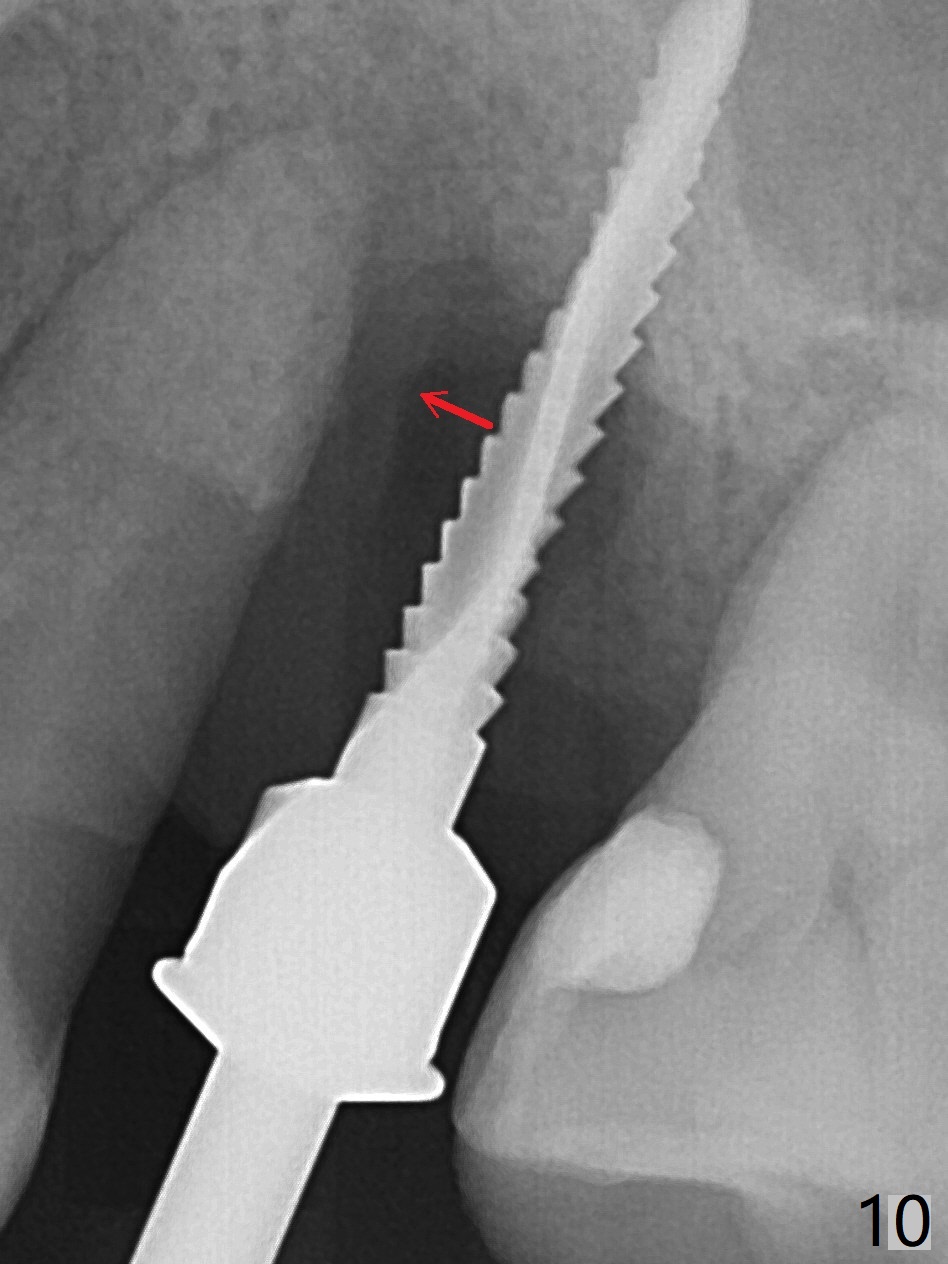

There is more bone apical to the residual root at #13 (Fig.1 red line). An immediate implant along the long axis of the root can be longer, 11.5 mm, favorable for primary stability (Fig.2 (CT taken immediately preop)). The initial trajectory is not ideal (Fig.3). When the pointed/Lindamann bur is removed (Fig.4), effort is made to move the apical end of the osteotomy distal (Fig.5 red arrow) by removing the apical bone (red dashed line). Following sequential osteotomy, a 4x10 mm dummy implant is placed with the trajectory remaining not so ideal (Fig.6,7). As the dummy implant is removed (Fig.8), a new osteotomy is established distal to the existing one (Fig.9). Subsequent drills gradually shift into the original osteotomy (Fig.10 red arrow). When the same dimension dummy implant returns, the trajectory improves with decreased stability (Fig.11). It seems reasonable to place a larger implant without further osteotomy. After placing PRF membrane and Vanilla graft for sinus lift (Fig.13 *), a 4.5x10 mm definitive implant is placed with loss of control in the trajectory (Fig.12,13).

When the initial osteotomy is off substantially (Fig.4), an osteotomy should be established de novo and as early as possible (Fig.14) so that subsequent osteotomy will not relapse to a great extent. More ideally, the initial osteotomy should be planned correctly (Fig.15,16) with sacrifice of the bone height. Nearly 1 month postop, the 4.5x5.5(5) cementation abutment is loose. When it is removed, the patient feels pain from the implant. A 5.5x6 mm healing abutment is placed instead. The implant osteointegrates with trabecular pattern in the sinus 9 months postop (Fig.20 *). The gingiva around the crown at #13 is healthy 1 year 4 months post cementation (Fig.18). Check the distal surface of #13 for bone loss if the tooth #14 is to be extracted.